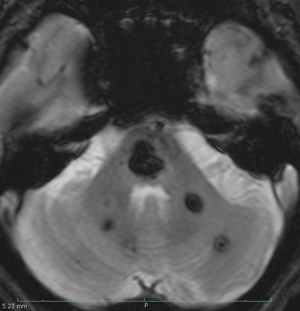

多発性海綿状血管腫 multiple cavernous hemangioma

家族性海綿状血管腫 familial cavernous hemangioma

この様な無数の海綿状血管腫を見ることがあります。多くの場合は家族性(遺伝性)の海綿状血管腫です。200個を超える海綿状血管腫があっても普通に何の障害もなく暮らしている患者さんもいます。脊髄の中にも発生しますから,脊髄のMRIもしていただきましょう。

小さな多発性の海綿状血管腫は,T2*(ティーツースター)という左の画像では見えるのですが,右にあるような普通のT1強調画像というのでははっきりみえません。